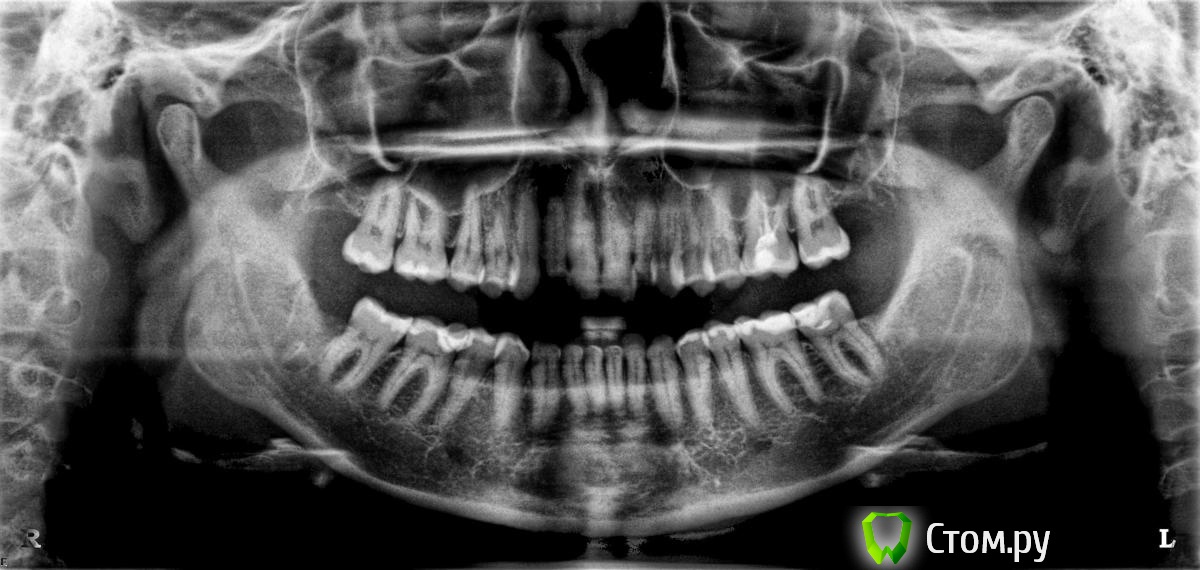

eva12 Опубликовано 8 апреля, 2014 Поделиться Опубликовано 8 апреля, 2014 (изменено) Доброго времени суток! Беспокоит 34 зуб если нажать на брекет, на 35 клиновидный дефект ( со слов доктора), 37( как мне кажется) есть повторный кариес, видна граница пломбы и я могу зацепиться за нее ногтем. Консультировалась в двух клиниках, постучали-посмотрели, сделали снимок и отпустили. Можно ли что-то увидеть на снимке с брекетами, мне кажется брекет закрывает пломбу и рассмотреть вторичный кариес невозможно, или я ошибаюсь? 34 зуб беспокоит очень, реагирует на горячее, что с ним делать? Выкладываю снимок до и во время лечения брекет-системой Изменено 8 апреля, 2014 пользователем eva12 Ссылка на комментарий

Гарриевич Опубликовано 9 апреля, 2014 Поделиться Опубликовано 9 апреля, 2014 Не ешьте горячего... Шутка)Вам нужен очной осмотр, по тем снимкам которые выложены ничего патологического не видно. Можете сделать прицельный снимок беспокоящих зубов и выложить, будет яснее картина Ссылка на комментарий

DmitrySH Опубликовано 9 апреля, 2014 Поделиться Опубликовано 9 апреля, 2014 Поддерживаю, на снимке ничего патологического не видно. Ссылка на комментарий